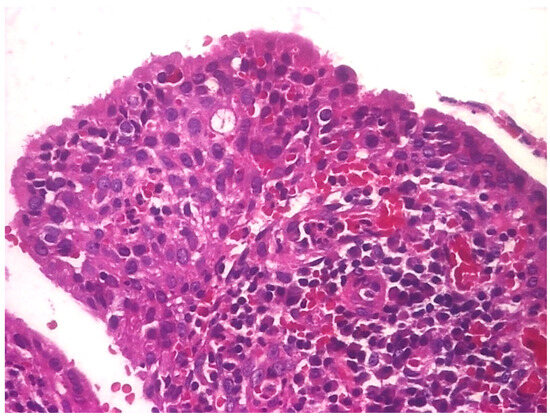

3.1.3. Analysis of Histopathologic and Immunohistochemical Results

| Histopathologic Aspects | Number of Patients |

|---|---|

| Cholesteatom | 276 |

| Polip | 180 |

| Tympanic membrane mucosa chamber, epithelium with apocrine-like cells, and chronic inflammatory infiltrate | 128 |

| Cell Types | Percentage |

| Lymphocytes T | 42.55% |

| Lymphocytes B | 31.45% |

| Macrophages | 26.00% |